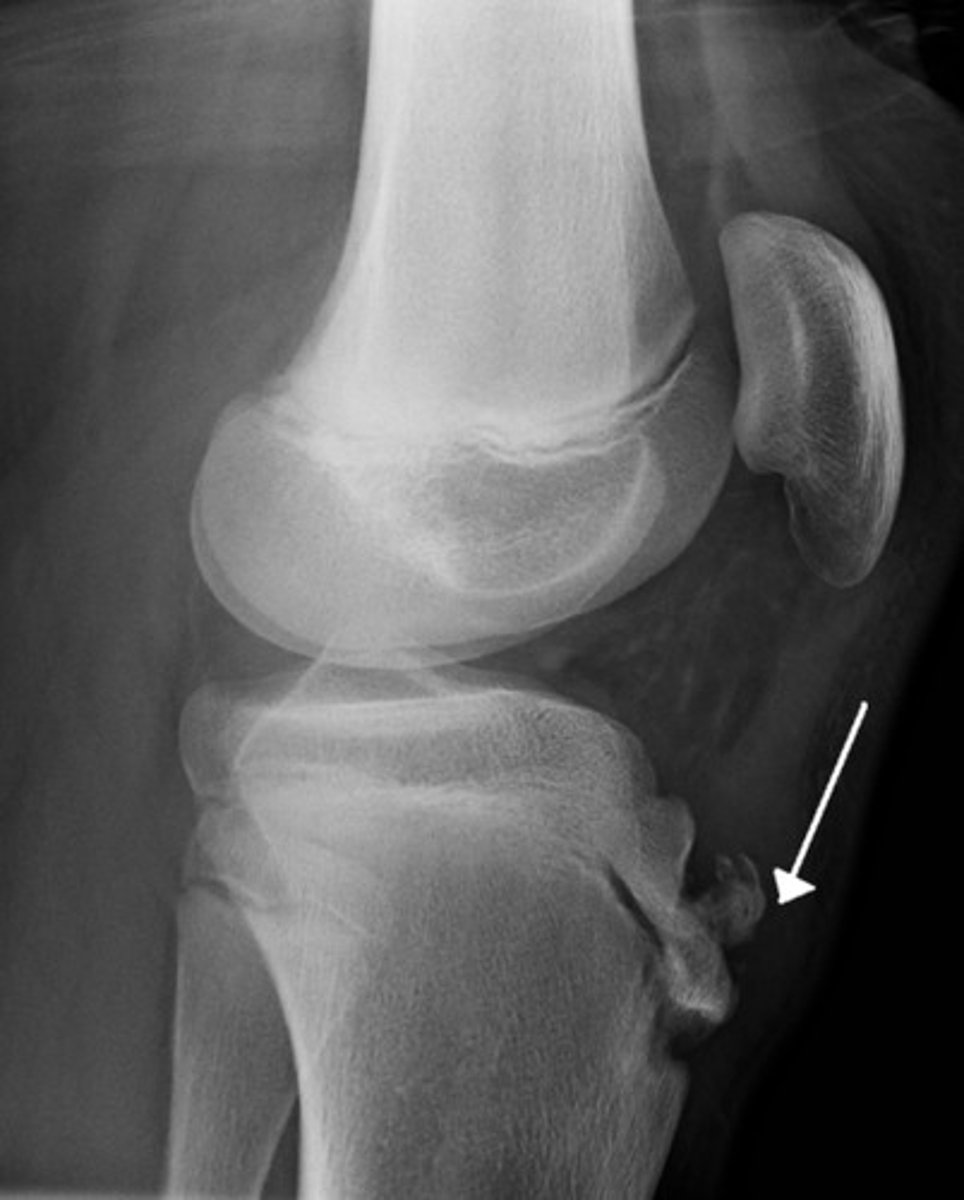

Edema + tenderness over tibial tubercle in athlete 13-14 male, quadriceps tendon puts traction on apophysis of the tibial tubercle where patellar tendon inserts.

Osgood-Schlatter dz common cause knee pain adolescent male athletes

- pain reproduces extending knee against resistant

- tx: activity restriction, stretching, NSAIDs

- X-ray show: soft tissue swelling, lifting tubercle from shaft, irregularity/fragmentation tubercle